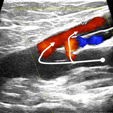

Hemodinámica venosa para un mejor diagnóstico y un tratamiento apropiado

C.H.I.V.A

Una partida de ajedrez contra la insuficiencia venosa crónica (IVC) de los miembros inferiores para restaurar el drenaje tisular preservando el sistema venoso y la VSI